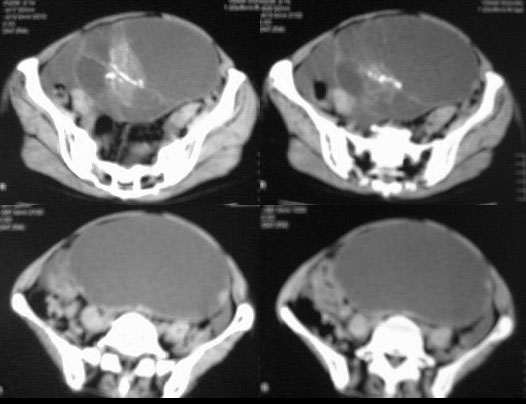

患者女性,45岁,因下腹疼痛,包块就诊,月经不太规则,其他未能提供有价值病史,请讨论

对不起各位,第一次试传,经验不足,补充一下资料,患者女性,45岁,因下腹疼痛,包块就诊,月经不太规则,其他未能提供有价值病史

卵巢囊腺癌伴腹膜转移可能性最大。

虽然没见到明显脂肪影,但是可见到明显钙化影,不排除恶性畸胎瘤的可能。

ct图像有点不连续,且大部画面模糊,有增强吗?就此而论我看向源于卵巢的,首先考虑囊腺ca或瘤.

此患者手术病理结果已出:卵巢囊腺瘤。